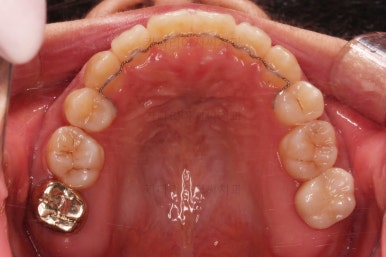

윗니는 좌측 작은 어금니가 한 개 모자랐고 아랫니는 앞니 하나가 모자라네요.

그런데 앞니는 아랫니가 1개 모자란 채로 교합이 맞춰져서 윗니가 하나 부족한 채로 애매한 상태였어요.

윗니만 추가적으로 발치를 1개 더 했어요.

아랫니는 최대한 추가 발치 없이 후방의 송곳니를 당겨와서 앞니 역할을 하게 했습니다.(총 4개 앞니처럼)

부분적으로 장치 셋팅을 다시 해줬고요.

밀고 당기기를 위해서 미니스크류를 셋팅했고요.